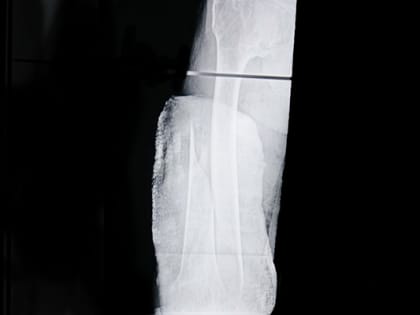

Закрытый перелом за две недели стал открытым

Как такое произошло? Одинокий мужчина 57 лет, возвращаясь домой в состоянии «подшофе», упал на лестничной клетке.